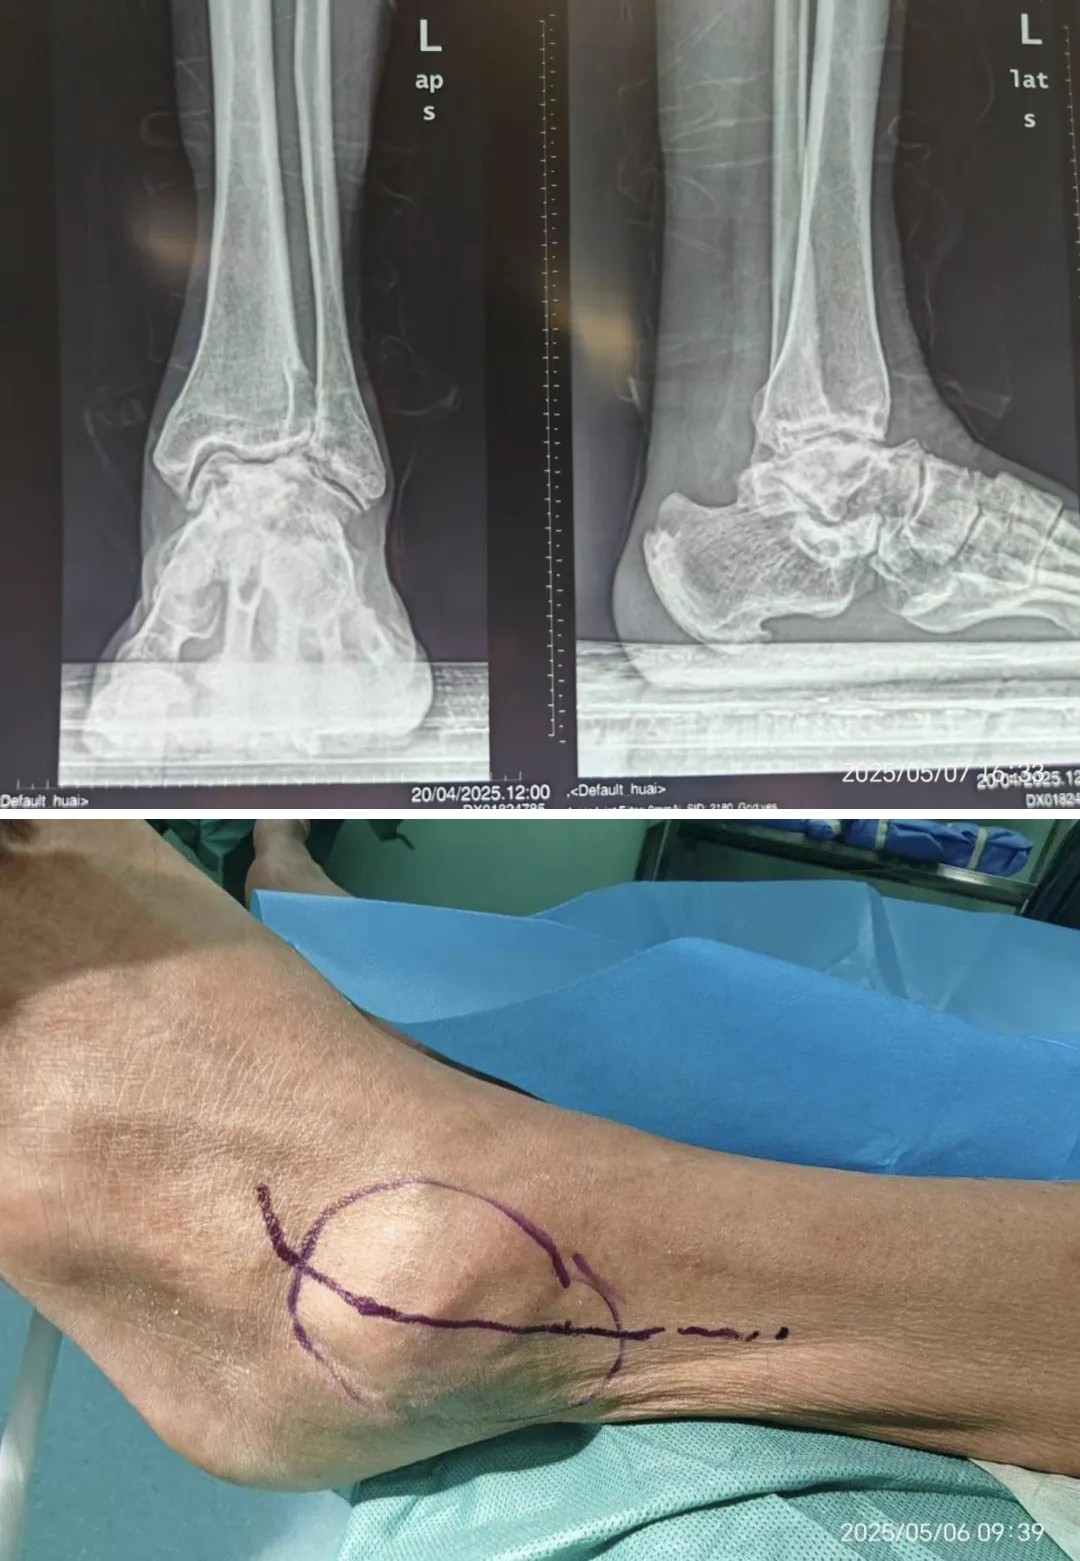

▲术前,踝关节外观显示关节变形、肿大,走路时局部疼痛明显

在山西省汾阳医院,患者行X线影像学检查发现:距骨存在塌陷性坏死;踝关节间隙弥漫性狭窄,关节边缘骨质增生伴关节面毛糙,且距下关节间隙变窄、伴关节面硬化及周围骨质增生。医生认为,其距骨坏死已引发多关节(踝关节、距下关节)受累的退行性关节炎改变,关节结构破坏及功能受损明显,为终末期创伤性踝关节炎伴距骨坏死。